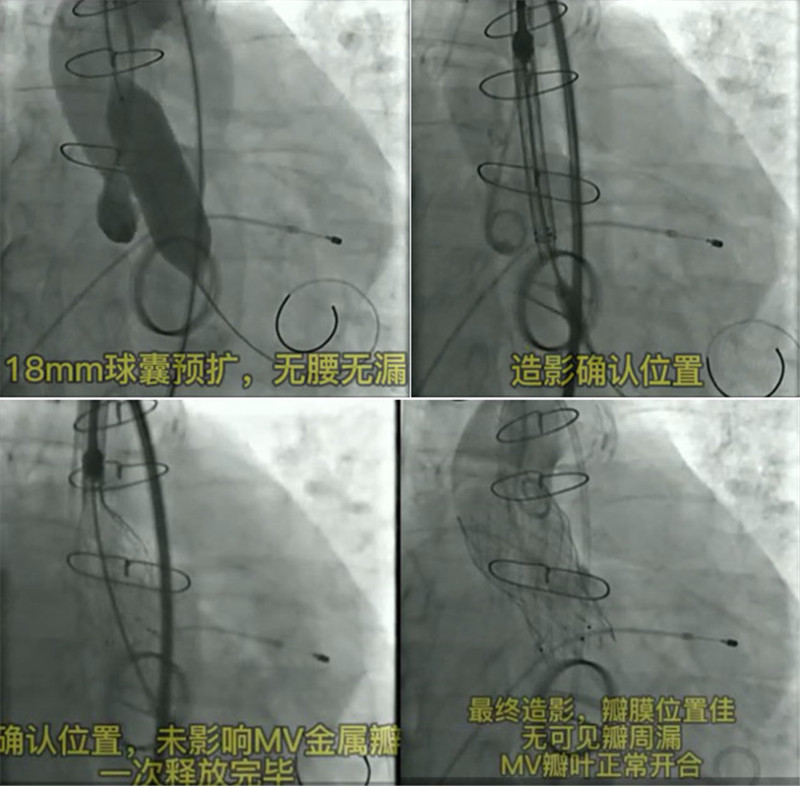

术中情况

手术顺利完成